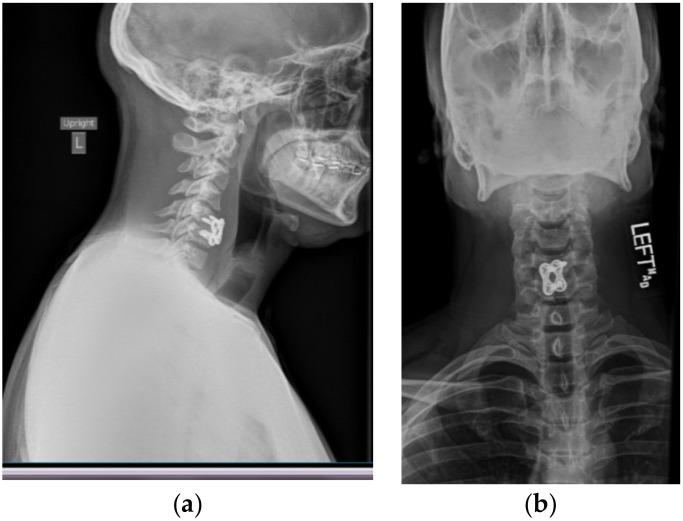

The authors report a case in which a 38-year-old male who presented himself to the emergency department with a chief complaint of cervical neck pain and paresthesia radiating from the right pectoral region down his distal right arm following self-manipulation of the patient's own cervical vertebrae. Initial emergency department imaging via cervical x-ray and magnetic resonance imaging (MRI) without contrast revealed no cervical fractures; however, there was evidence of an acute cervical disc herniation (C3-C7) with severe herniation and spinal stenosis located at C5-C6. Immediate discectomy at C5-C6 and anterior arthrodesis was conducted in order to decompress the cervical spinal cord. Acute traumatic cervical disc herniation is rare in comparison to disc herniation due to the chronic degradation of the posterior annulus fibrosus and nucleus pulposus. Traumatic cervical hernias usually arise due to a very large external force causing hyperflexion or hyperextension of the cervical vertebrae. However, there have been reports of cervical injury arising from cervical spinal manipulation therapy (SMT) where a licensed professional applies a rotary force component. This can be concerning, considering that 12 million Americans receive SMT annually (Powell, F.C.; Hanigan, W.C.; Olivero, W.C. A risk/benefit analysis of spinal manipulation therapy for relief of lumbar or cervical pain. , , 73-79.). This case study involved an individual who was able to apply enough rotary force to his own cervical vertebrae, causing severe neurological damage requiring surgical intervention. Individuals with neck pain should be advised of the complications of SMT, and provided with alternative treatment methods, especially if one is willing to self manipulate.

作者报告了一例病例,一名38岁男性因自行推拿颈椎后出现颈部疼痛和从右胸区域向下放射至右上肢远端的感觉异常为主诉前来急诊科就诊。急诊科最初通过颈椎X线和无造影剂的磁共振成像(MRI)检查未发现颈椎骨折;然而,有证据显示存在急性颈椎间盘突出(C3 - C7),其中C5 - C6处有严重突出及椎管狭窄。随即对C5 - C6进行了椎间盘切除术及前路椎间融合术,以减压颈脊髓。与因纤维环后部和髓核慢性退变导致的椎间盘突出相比,急性创伤性颈椎间盘突出较为罕见。创伤性颈椎间盘突出通常是由于非常大的外力导致颈椎过度前屈或后伸引起的。然而,有报告称颈椎脊柱推拿疗法(SMT)(有执照的专业人员施加旋转力成分)可导致颈部损伤。鉴于每年有1200万美国人接受SMT(鲍威尔,F.C.;哈尼根,W.C.;奥利韦罗,W.C. 脊柱推拿疗法缓解腰或颈疼痛的风险/效益分析。 , ,73 - 79.),这可能令人担忧。本病例研究涉及一名能够对自己的颈椎施加足够旋转力,导致严重神经损伤并需要手术干预的个体。对于颈部疼痛的个体,应告知其SMT的并发症,并提供替代治疗方法,尤其是对于那些愿意自行推拿的人。